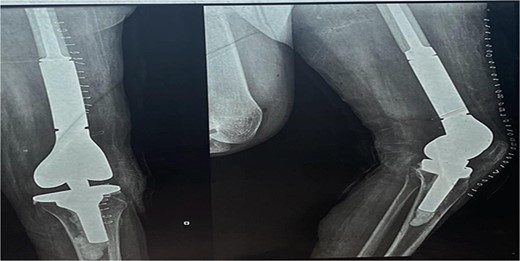

The X-ray after surgery showed a mega prosthesis with good implant alignment.

Postoperative care included continuing antibiotics for two weeks, pain management, and initiating a passive range of motion exercises the next day. The immediate postoperative period was uneventful, and postoperative X-rays confirmed the proper placement and alignment of the prosthesis. The patient was mobilized with the help of physiotherapy, and her mobility gradually improved. She was scheduled for regular follow-up visits to monitor her recovery and the status of her pregnancy.